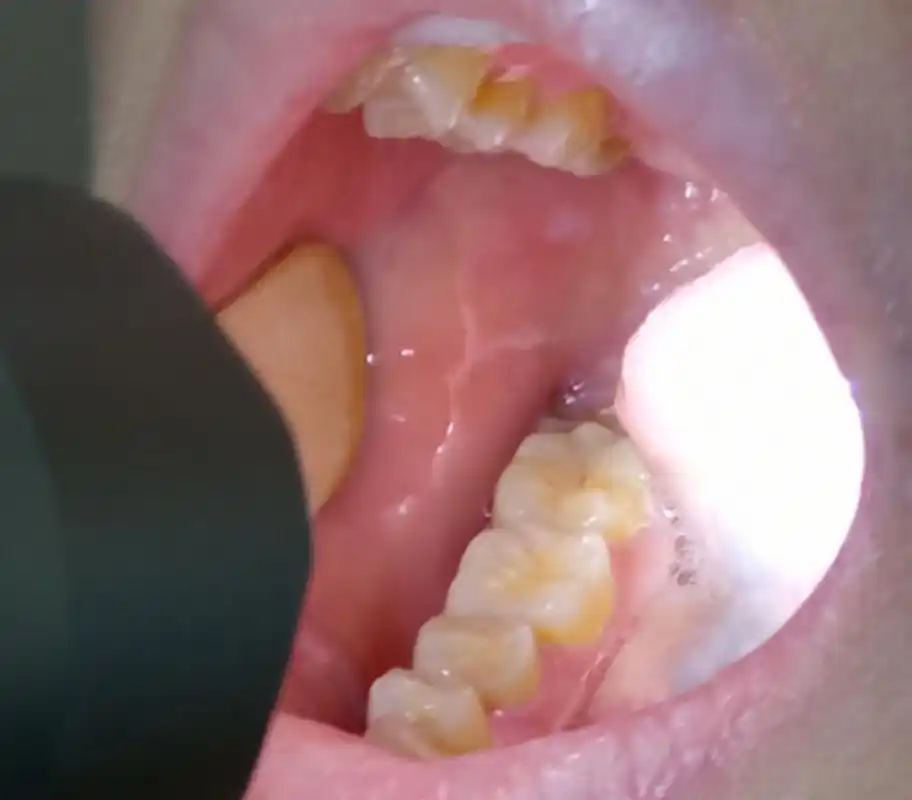

口腔白斑危害大,要及时治疗!

在口腔扁平苔藓,口腔白斑症,口腔癌等疾病中较为常见.

口腔内壁出现白斑先别慌!这三种治疗方法,请你记下